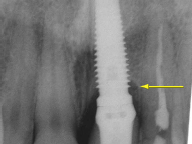

Regular x-rays help to find problems that may not be visible. Decay has been found underneath this bridge (yellow arrow). If left untreated, the tooth and the entire bridge may be lost.

Bone loss around an implant may also be found on an x-ray (yellow arrow). This type of bone loss is not painful, but if left untreated, the implant may be lost.